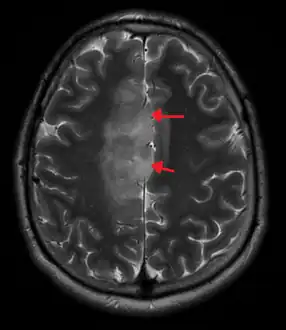

An X-ray computed tomography (CT) or magnetic resonance imaging (MRI) scan is necessary to characterize the anatomy of this tumor as to size, location, and its heter/homogeneity. However, final diagnosis of this tumor, like most tumors, relies on histopathologic examination (biopsy examination).[3]

If resected, the surgeon will remove as much of this tumor as possible, without disturbing eloquent regions of the brain (speech/motor cortex) and other critical brain structure. Thereafter, treatment may include chemotherapy and radiation therapy of doses and types ranging based upon the patient's needs. Subsequent MRI examination are often necessary to monitor the resection cavity.